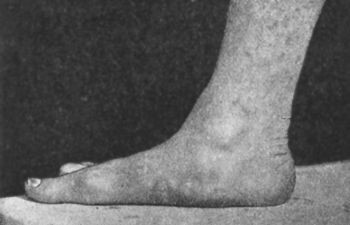

275 144.Congenital Talipes Equino-varus in a Man

277 145.Bilateral Pes Equinus in a Boy

285 150.Pes Cavus in Association with Pes Equinus, the Result of Poliomyelitis

286 151.Radiogram of Foot of Adult, showing Changes in the Bones in Pes Cavus